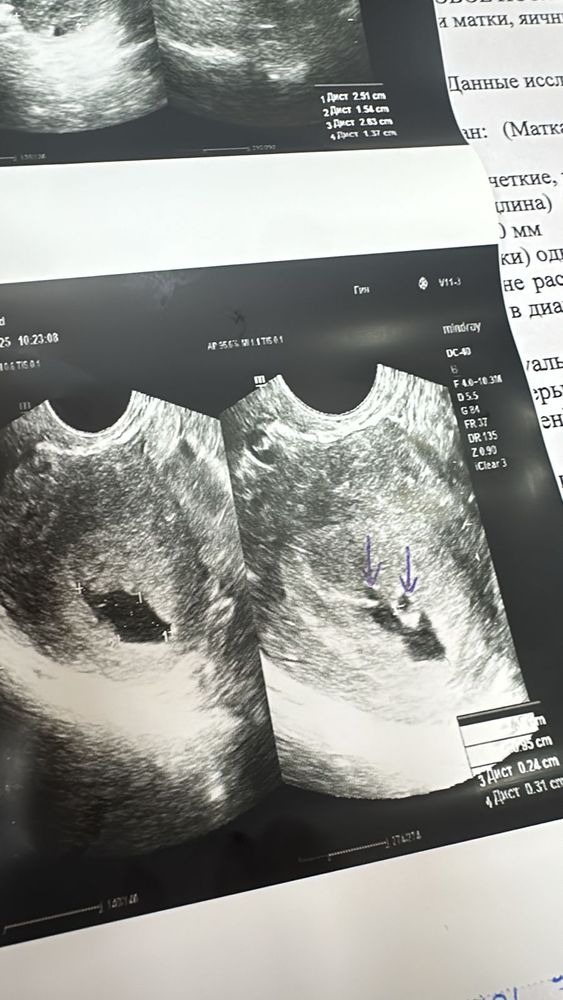

Здравствуйте. Я беременна. Первый день последних месячных до 10 го декабря 2024 года. Первый УЗИ 16.01.2025 года. Поставили срок 3-4 недели. Двойня под вопросом. И гематому с размером 18*3 мм. Повторный УЗИ 23.01.2025 двойную подтвердили. Но один меньше другого. И гематома выросла почти в два раза.

Обе УЗИ прикреплю